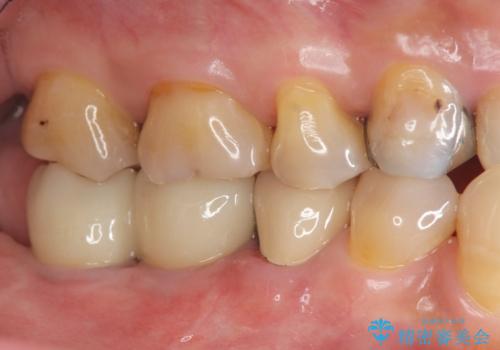

- 「奥歯で噛むと痛い、いつも膿のにおいがして不快、改善してほしい。」と治療を希望され来院されました。

精査した結果、奥歯の根は破折しており抜歯を避けられない状況でした。

咬合力が強く、その他の歯の破折も防ぐために奥歯の咬合機能をインプラントを用いて回復する治療計画を立てます。